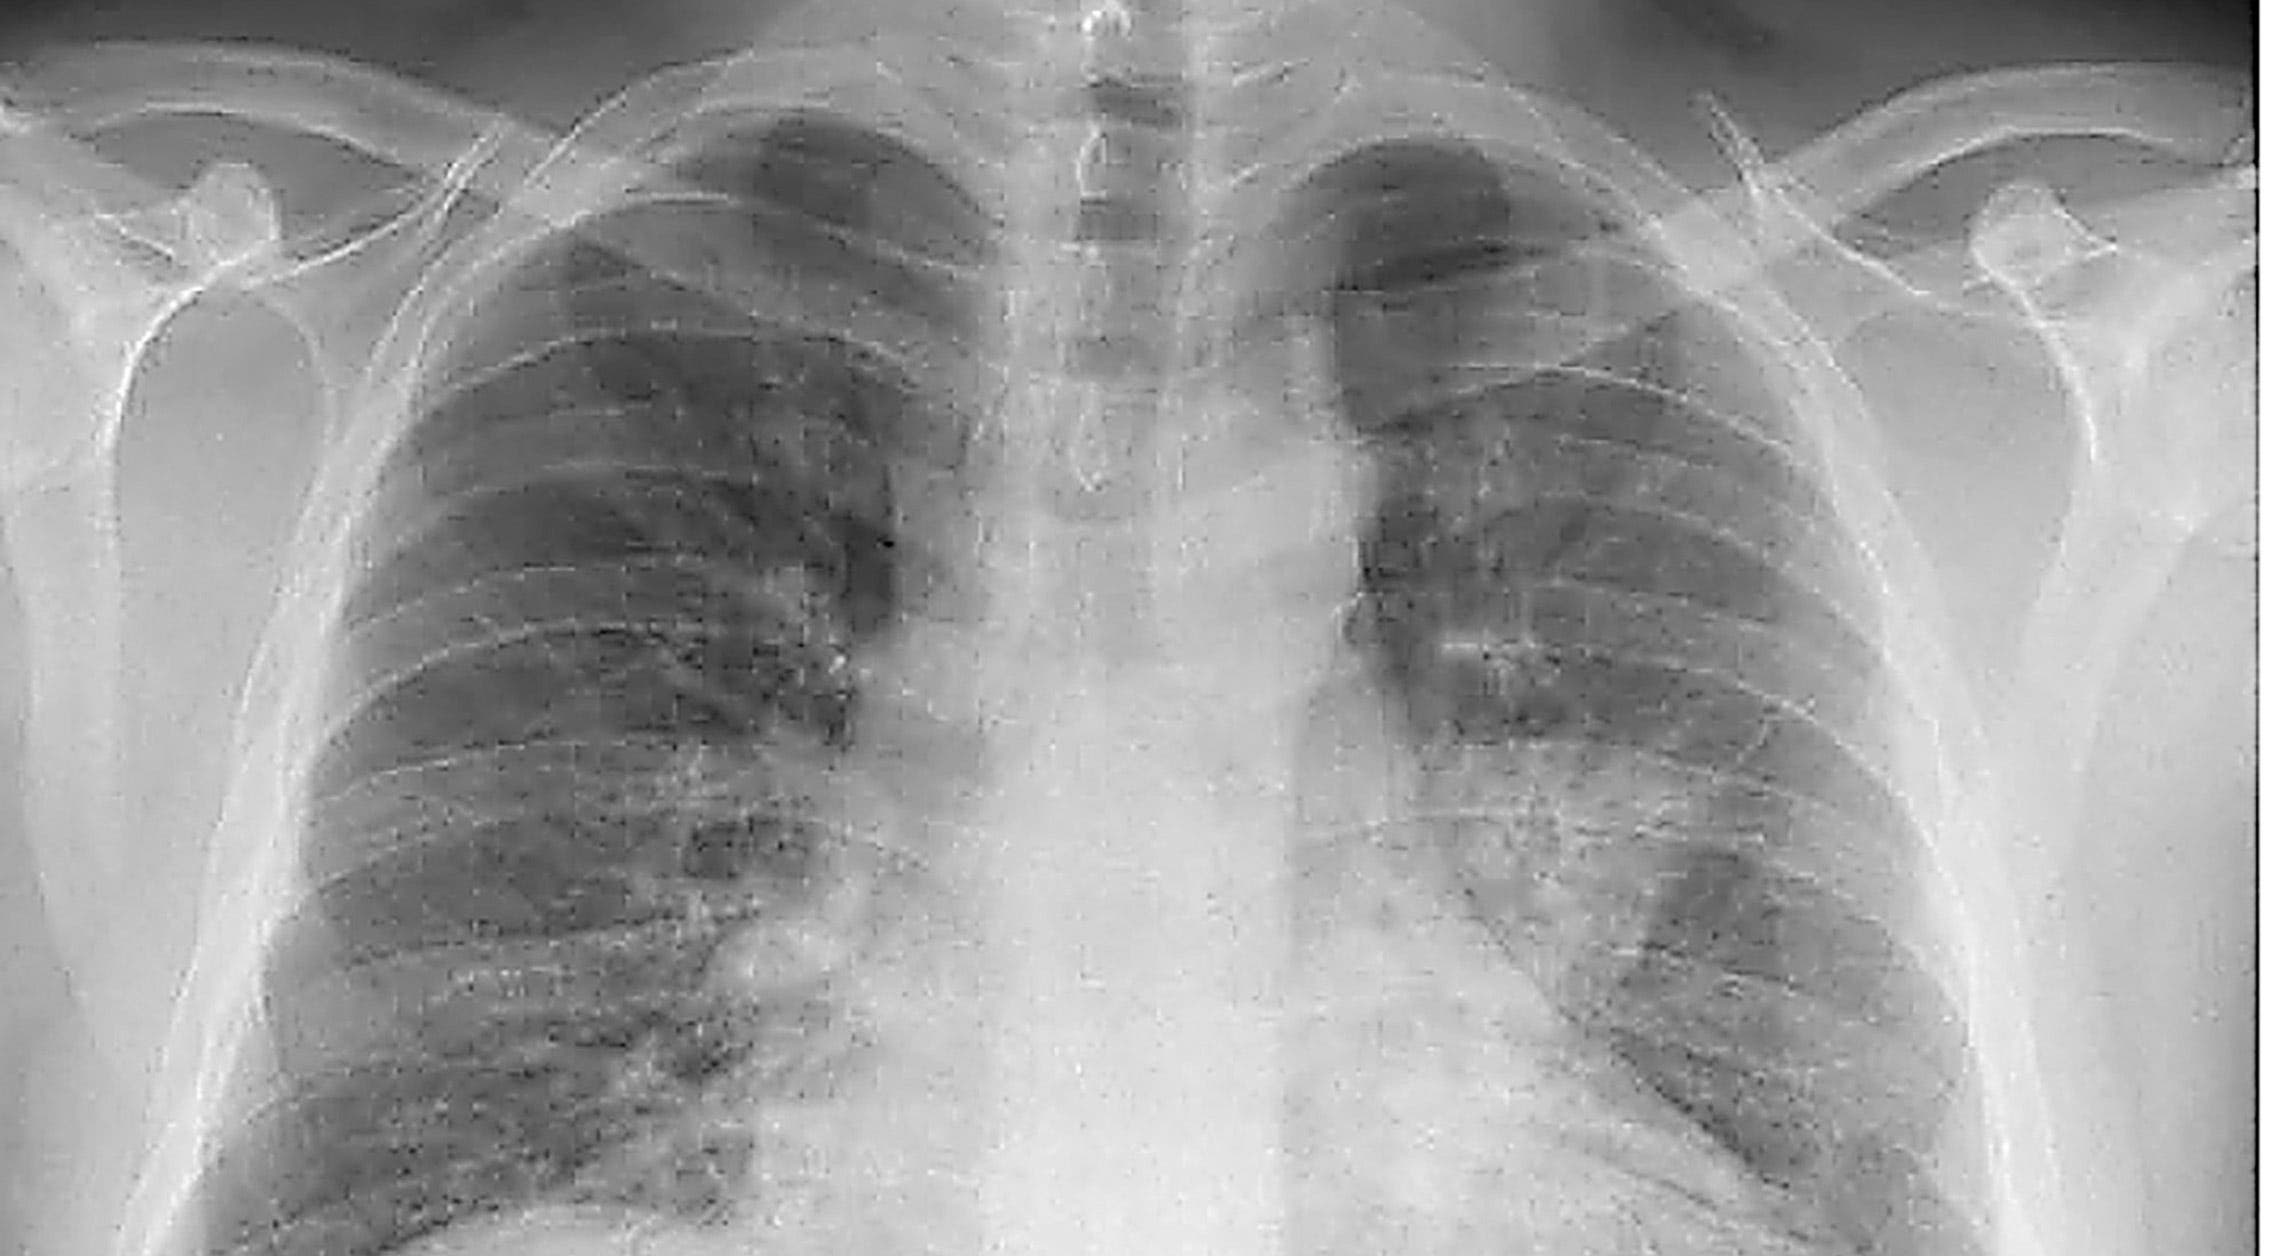

EVOLUCIÓN. Neumonía viral primaria por gripe A (H1N1) en paciente de 43 años perteneciente a grupo de riesgo.